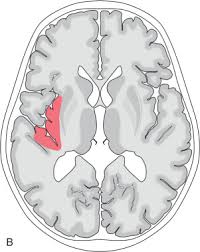

Lesions similar to cytotoxic edema, and lesions similar to vasogenic edema. Seizure, altered sensorium, fever frontal and temporal lobes, rarely extratemporal t2 hyperintensity, restricted diffusion, sometimes. Herpes encephalitis is the most common sporadic encephalitis in the united states and other industrialized countries .occurring as either a primary infection with herpes simplex virus or as a reactivation of latent virus, herpes encephalitis causes significant morbidity and mortality .early intervention with acyclovir significantly improves outcome; The clinical syndrome is often characterized by the rapid onset of fever, headache, seizures, focal neurologic signs, and impaired consciousness 1 . Having said that, mri with contrast is considered the most sensitive imaging modality, and findings are present in over half of individuals 8. The patients with the former type of lesions had fulminating disease, and were in severe clinical condition. Herpes simplex encephalitis occurs as 2 distinct entities: 4 it was found that, rather surprisingly, varicella zoster virus (vzv), the cause of chickenpox and herpes zoster, was the most frequently detected virus at 29%, with hsv and enteroviruses accounting for 11% of cases. Two subtypes are recognized which differ in demographics, virus, and pattern of involvement. (1)department of radiology, ankara numune education and research hospital, ankara, turkey. Neonatal herpes simplex encephalitis is caused by vertical transmission of infection during passage from birth canal with diffuse cerebral involvement within the first month after birth; As the older term limbic encephalitis implies, the most common location of involvement is the mesial temporal lobes and limbic systems, typically manifested by cortical thickening and increased t2/flair. In patients with herpes encephalitis, two distinct types of diffusion imaging findings (on b =1000 s/mm 2 images, and adc maps) were noted:

For viral infection of the meninges, please refer to the general article on viral meningitis, and, for a broad view on the curriculum of infections of the central nervous system, refer to cns. Two subtypes are recognized which differ in demographics, virus, and pattern of involvement. A recent study in finland also used pcr to detect various viruses in the csf of over 3000 patients who had infections of the cns including encephalitis, meningitis, and myelitis. The patients with the former type of lesions had fulminating disease, and were in severe clinical condition. Despite advances in antiviral therapy over the past 2 decades, herpes simplex encephalitis (hse) remains a serious illness with significant risks of morbidity and death. Normal mr imaging findings (type 1, 53% of patients), isolated hippocampal involvement (type 2, 13%), other brain lesions without hippocampal involvement (type 3, 13%), and other brain lesions with hippocampal involvement (type 4, 21%). Lesions similar to cytotoxic edema, and lesions similar to vasogenic edema. As the older term limbic encephalitis implies, the most common location of involvement is the mesial temporal lobes and limbic systems, typically manifested by cortical thickening and increased t2/flair.

The patients with the former type of lesions had fulminating disease, and were in severe clinical condition. The diagnosis of hse is based on laboratory investigations, magnetic resonance (mr) imaging findings, electroencephalogram and, occasionally, a biopsy. Herpes encephalitis is the most common sporadic encephalitis in the united states and other industrialized countries .occurring as either a primary infection with herpes simplex virus or as a reactivation of latent virus, herpes encephalitis causes significant morbidity and mortality .early intervention with acyclovir significantly improves outcome; Herpes simplex (hsv) encephalitis is the most common cause of fatal sporadic fulminant necrotising viral encephalitis and has characteristic imaging findings. In patients with herpes encephalitis, two distinct types of diffusion imaging findings (on b =1000 s/mm 2 images, and adc maps) were noted: Relapse of encephalitis occurs in up to 10% of patients, manifested by recurrent symptoms, clinical and mri findings, and the presence of herpes simplex virus type 1 dna in the cerebrospinal fluid (csf). In children older than 3 months and in adults, hse is usually localized to the temporal and frontal lobes and is c. In patients with herpes encephalitis, two distinct types of diffusion imaging findings (on b =1000 s/mm 2 images, and adc maps) were noted: Herpes simplex (hsv) encephalitis is the most common cause of fatal sporadic fulminant necrotizing viral encephalitis and has characteristic imaging findings. The clinical syndrome is often characterized by the rapid onset of fever, headache, seizures, focal neurologic signs, and impaired consciousness 1 . We present mri findings of two cases of herpes simplex encephalitis (hse) confirmed by pcr analysis, focusing on the serial changes after acyclovir therapy: Two subtypes are recognised which differ in demographics, virus, and pattern of involvement. Despite advances in antiviral therapy over the past 2 decades, herpes simplex encephalitis (hse) remains a serious illness with significant risks of morbidity and death.